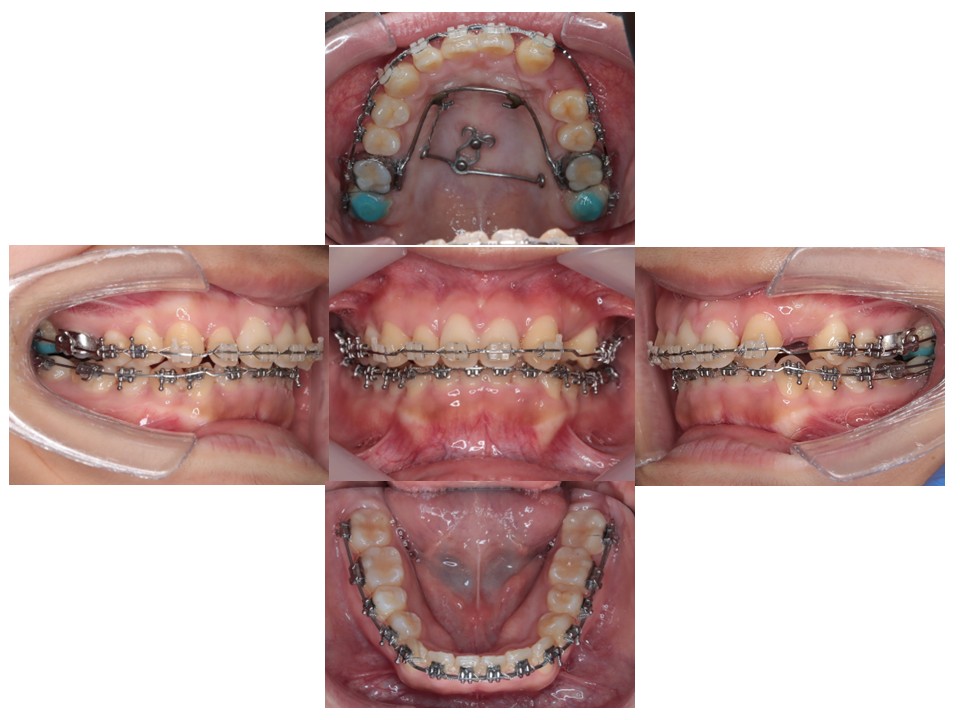

治療経過

左上奥歯、左下の奥歯をアンカースクリュー(ネジ)を使って後方に引っ張り、歯を並べるスペースを作っている。

上の歯のスペースを閉じています

治療結果

上下顎前歯の深いかみ合わせとガタガタの改善を認めた

治療期間:2年8ヶ月